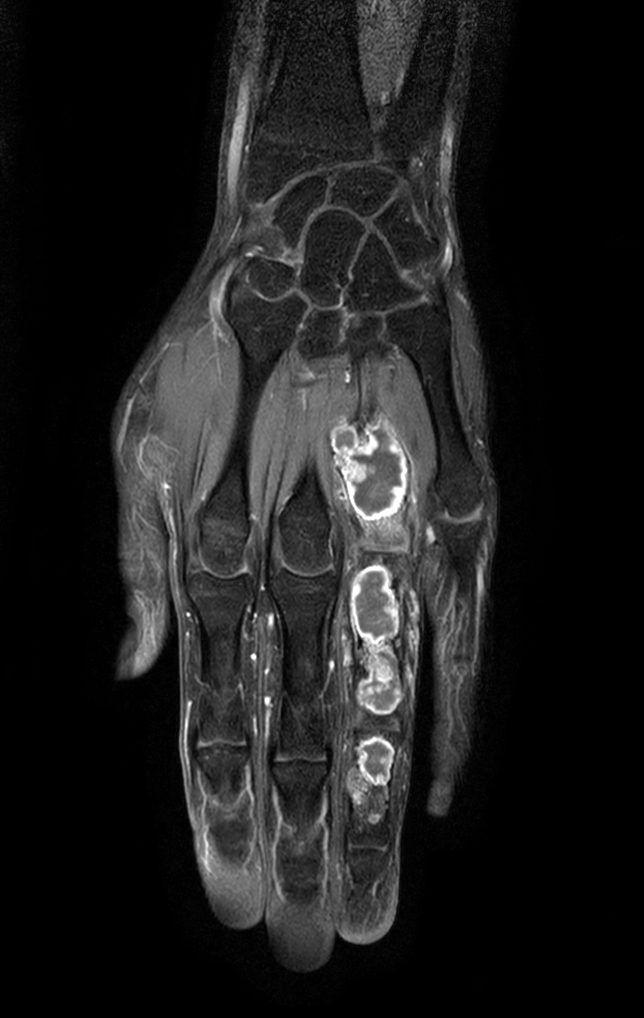

Coronal T1w mDIXON XD TSE (Water only)

Coronal T1w mDIXON XD TSE (In Phase)

Coronal T1w mDIXON XD TSE (Partial FatSat)

Coronal T1w mDIXON XD TSE (Water only) (with gado)

Coronal T1w mDIXON XD TSE (In Phase) (with gado)

Coronal T1w mDIXON XD TSE (Partial FatSat) (with gado)